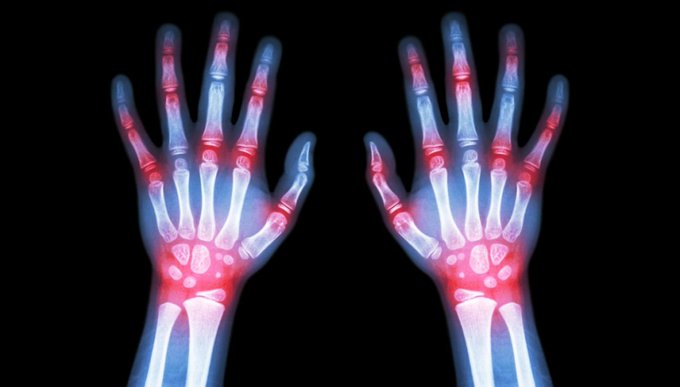

La Professoressa Reumatologia Università di Torino e Presidente EULAR, Anna Maria Iagnocco, e il Direttore SC Reumatologia AOU Città della Salute e della Scienza di Torino, Enrico Fusaro, concordano che l’artrite reumatoide è una malattia cronica sistemica per la quale è cruciale una diagnosi precoce ed un trattamento efficace, sin dalle fasi iniziali di patologia. L’ottimizzazione del trattamento consente di bloccare la flogosi o limitare la sua severità, prevenendo lo sviluppo del danno irreversibile che condurrebbe irrimediabilmente alla disabilità.